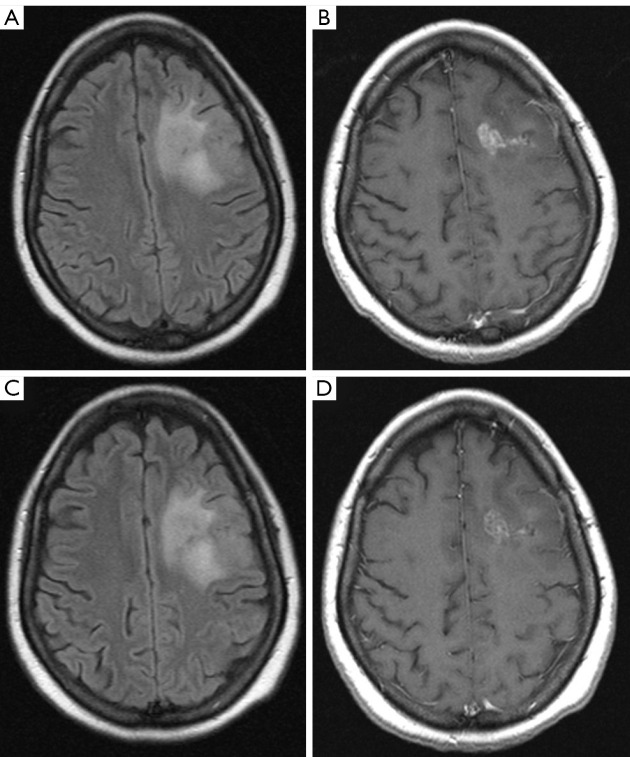

背景:2018年提出了一种新的成人脑肿瘤治疗后磁共振成像分类和报告系统,命名为脑肿瘤报告和数据系统(BT-RADS),需要通过协议研究的方式进行验证。方法:采用回顾性研究方法,对在法国国立政治医学基金会(Fondazione Policlinico Campus Bio-Medico)进行随访的原发性脑肿瘤成年患者进行磁共振成像(MRI)检查。4名放射科医生(2名住院放射科医生,1名普通放射科医生,1名神经放射科医生)阅读并使用BT-RADS评分工具对每项研究进行评分,对MRI原始报告不知情。计算观察者间一致性和Fleiss’k来评估诊断一致性的水平。评估了多少次分配不同的BT-RADS评分会导致不同的患者管理。结果:纳入研究的患者总数为23例,mri 147例,回顾性评估BT-RADS评分588分。两种最常见的肿瘤类型是星形细胞瘤4级(62%)和少突胶质细胞瘤3级(21%)。所有4位放射科医生的总体一致性率为82%,Fleiss’k为0.70。普通放射科医生和神经放射科医生的总体一致性为91%,Fleiss’k为0.86。2名放射科住院医师与神经放射科医师的总体一致性率为80%,Fleiss’k为0.66。星形细胞瘤3级(k: 0.51)和少突胶质细胞瘤2级(k: 0.32)的一致性较差,而星形细胞瘤4级(k: 0.70)、星形细胞瘤2级(k: 0.78)和少突胶质细胞瘤3级(k: 0.78)的一致性较高。所有放射科医生同意70%患者的BT-RADS分配,三位放射科医生同意17%,两位放射科医生同意13%。在任何情况下,读者之间都没有完全的分歧。在18%的病例中,估计的BT-RADS的差异会导致不同的后续管理。结论:对于神经放射科医生和放射科医生来说,BT-RADS可以被认为是一种有效的工具,即使他们在成人原发性脑肿瘤随访期间对患者图像的解释经验很少,也可以支持标准化的解释、报告和临床管理。

Methods: A retrospective study was designed with the aim of identifying contrast-enhanced magnetic resonance imaging (MRI) of adult patients on follow-up for primary brain tumor at Fondazione Policlinico Campus Bio-Medico. Four radiologists (2 radiology residents, 1 general radiologist, 1 neuroradiologist) read and scored each study using the BT-RADS scoring tool, blinded to the MRI original report. Interobserver agreement and Fleiss' k were calculated to assess the level of diagnostic agreement. It was assessed how many times the assignment of different scoring of BT-RADS would have led to a different patient management.

Results: The total number of patients included in the study was 23 with 147 MRIs and a total of 588 BT-RADS scores retrospectively evaluated. The two most frequent tumor types were astrocytoma grade 4 (62%) and oligodendroglioma grade 3 (21%). The overall agreement rate for all 4 radiologists was 82% with a Fleiss' k of 0.70. The overall agreement rate between general radiologist and neuroradiologist was 91% with a Fleiss' k of 0.86. The overall agreement rate between 2 radiology residents and neuroradiologist was 80% with a Fleiss' k of 0.66. Astrocytoma grade 3 (k: 0.51) and oligodendroglioma grade 2 (k: 0.32) showed a poor agreement while higher values of agreement were found for astrocytoma grade 4 (k: 0.70), astrocytoma grade 2 (k: 0.78) and oligodendroglioma grade 3 (k: 0.78). All the radiologists agreed on BT-RADS assignment in 70% patients, three radiologists agreed in 17% and two radiologists agree in 13%. In no cases there was a complete disagreement among the readers. In 18% of cases the discrepancy in the estimated BT-RADS would have led to a different follow-up management.